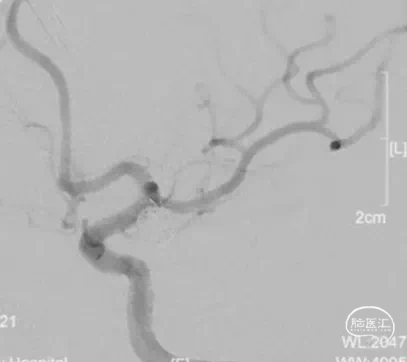

术前影像

术前影像